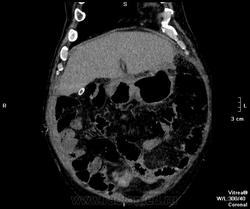

Пациент оперирован по поводу аденоКа толстого кишечника, гемиколэктомия. Онкопоиск, поиск вторичного поражения.

В воротах печени беда, но не об этом сейчас. Прицельно смотрим контраст.

отсроченные

Во втором случае наблюдается гиподенсный участок в печени.

дифференцируем между метастазом и холангиокарциномой

Случай 2. Опять не попали в фазы, рано. Исследование малоинформативно по сути(. Какова скорость введения автошприцем? Катетер кубитальный или в запястье?